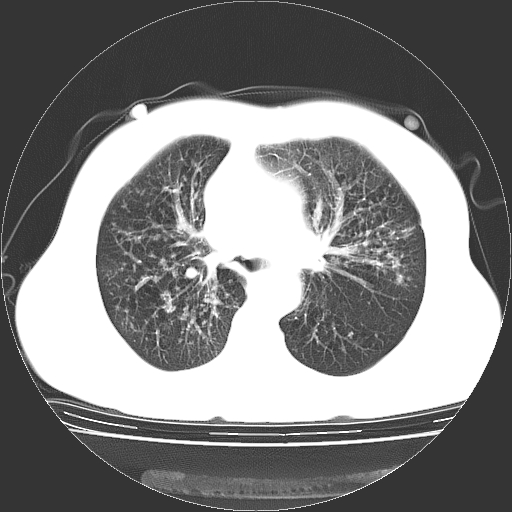

标题: CT23067:女,70岁,咳嗽、咳痰一个月,低热一周。 [打印本页]

女,70岁,咳嗽、咳痰一个月,低热一周。

1.左上肺结核,部分纤维化。右肺中下叶部分肺不张,内见液化、坏死及点状钙化,右中下叶支气管壁增厚、管腔狭窄,见多个点状钙化,结合临床考虑支气管内膜结核,建议痰检查抗酸杆菌并参考血沉。两肺多个小圆点状高密度灶,境界模糊,多考虑结核肺内播散。但本人年龄较大首先应支气管镜检以除外右肺癌。